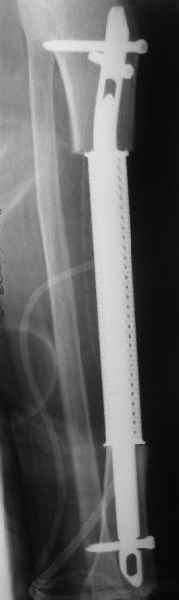

Пациентке дважды делали биопсию, второй раз - довольно расширенную, через доступ 5 см. Стекла смотрели в онкодиспансере и у нас, морфологи единодушно поставили гигантоклеточную опухоль. Диафизарная локализация для которой очень нехарактерна, 1-2%.

Исходя из диагноза, выглядела адекватной сегментарная резекция, которая дает наименьшее количество рецидивов.

Напомню, пациентке 61 год, она еще практически слепая, т.е. функциональные потребности невысокие. Больную положили к нам в отделение. Заказали кейдж в МАТИ (посодействовал Анатолий Федорович Лазарев, ему огромное спасибо), его быстро сделали. На этой неделе состоялась операция - сделали сегментарную резекцию единым блоком. Кортикальная пластинка вроде не не была нигде прорвана, хотя местами сильно истончена.

Пока делали остеосинтез, препарат успели отправить в лабораторию, так что распилить получилось только на следующий день.

При его рассмотрении с рентгенологом и морфологом сошлись, что это не фиброзная дисплазия, что было первым предположением по рентгенограммам. В полости было и мягкотканое образование. Окончательно заключение дадут через несколько дней. Будем признательны за комментарии и критику.